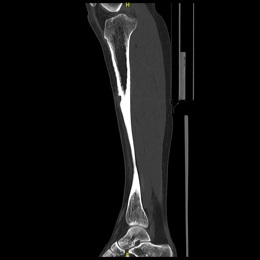

38E) Sagittal CT Of Right Tibia Osteoblastoma

Radiographic imaging is used to help form a diagnosis. These include X-Ray, MRI, CT and Bone Scans

An example of an CT is shown.